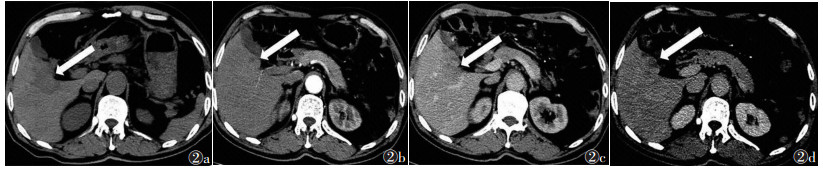

2 结果5例中,粟粒型肝结核2例,结节型肝结核3例。①粟粒型肝结核:CT图像上均可见肝脏增大,1例可见脾脏增大;2例均可见肝内散在多发小囊样低密度灶(1例伴小钙化灶),直径0.6~2.0 cm,动脉期、静脉期及延迟期均无强化(图 1)。②结节型肝结核:病灶直径均>2.0 cm,表现为肝内单发或多发略低密度灶,CT值41~50 HU,增强扫描延迟期轻度强化,1例病灶内可见“簇征”或“蜂窝征”(图 2)。

| 图 2 男,64岁,结节型肝结核 图 2a~2d 分别为CT平扫、增强扫描动脉期、门静脉期和延迟期图像。平扫肝内可见单发略低密度灶(白箭),CT值为43 HU,注射对比剂后动脉期轻度强化,门静脉期病灶持续强化、门静脉左支轻度受压,延迟期病灶内部可见“簇征”、“蜂窝征”(白箭) |